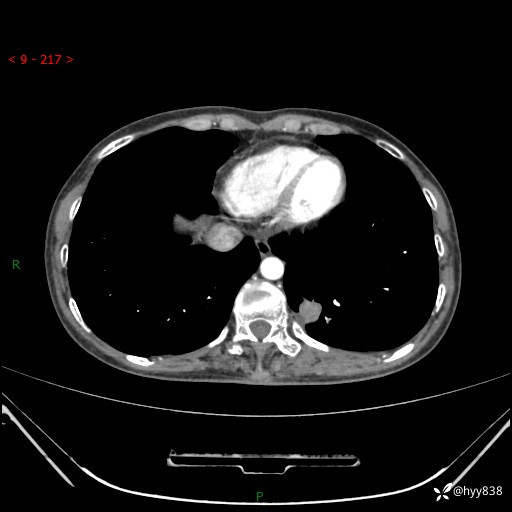

胸部CT平扫

增强动脉期+静脉期

各期CT值:48hu 65hu 76hu